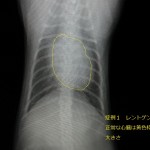

1つ目は若い猫ちゃん、去勢手術で術前検査を実施しました。

すごく元気な子でなにも症状もありませんでしたが、

レントゲンをとったら・・・心臓が大きい!

聴診では心臓の雑音は聴かれませんでした。

レントゲンでは大きさが大きいということ以外はわかりませんので、

エコー検査で内部構造や異常の部位の検査に入ります。

エコー検査で心室中隔欠損症がみつかりました。